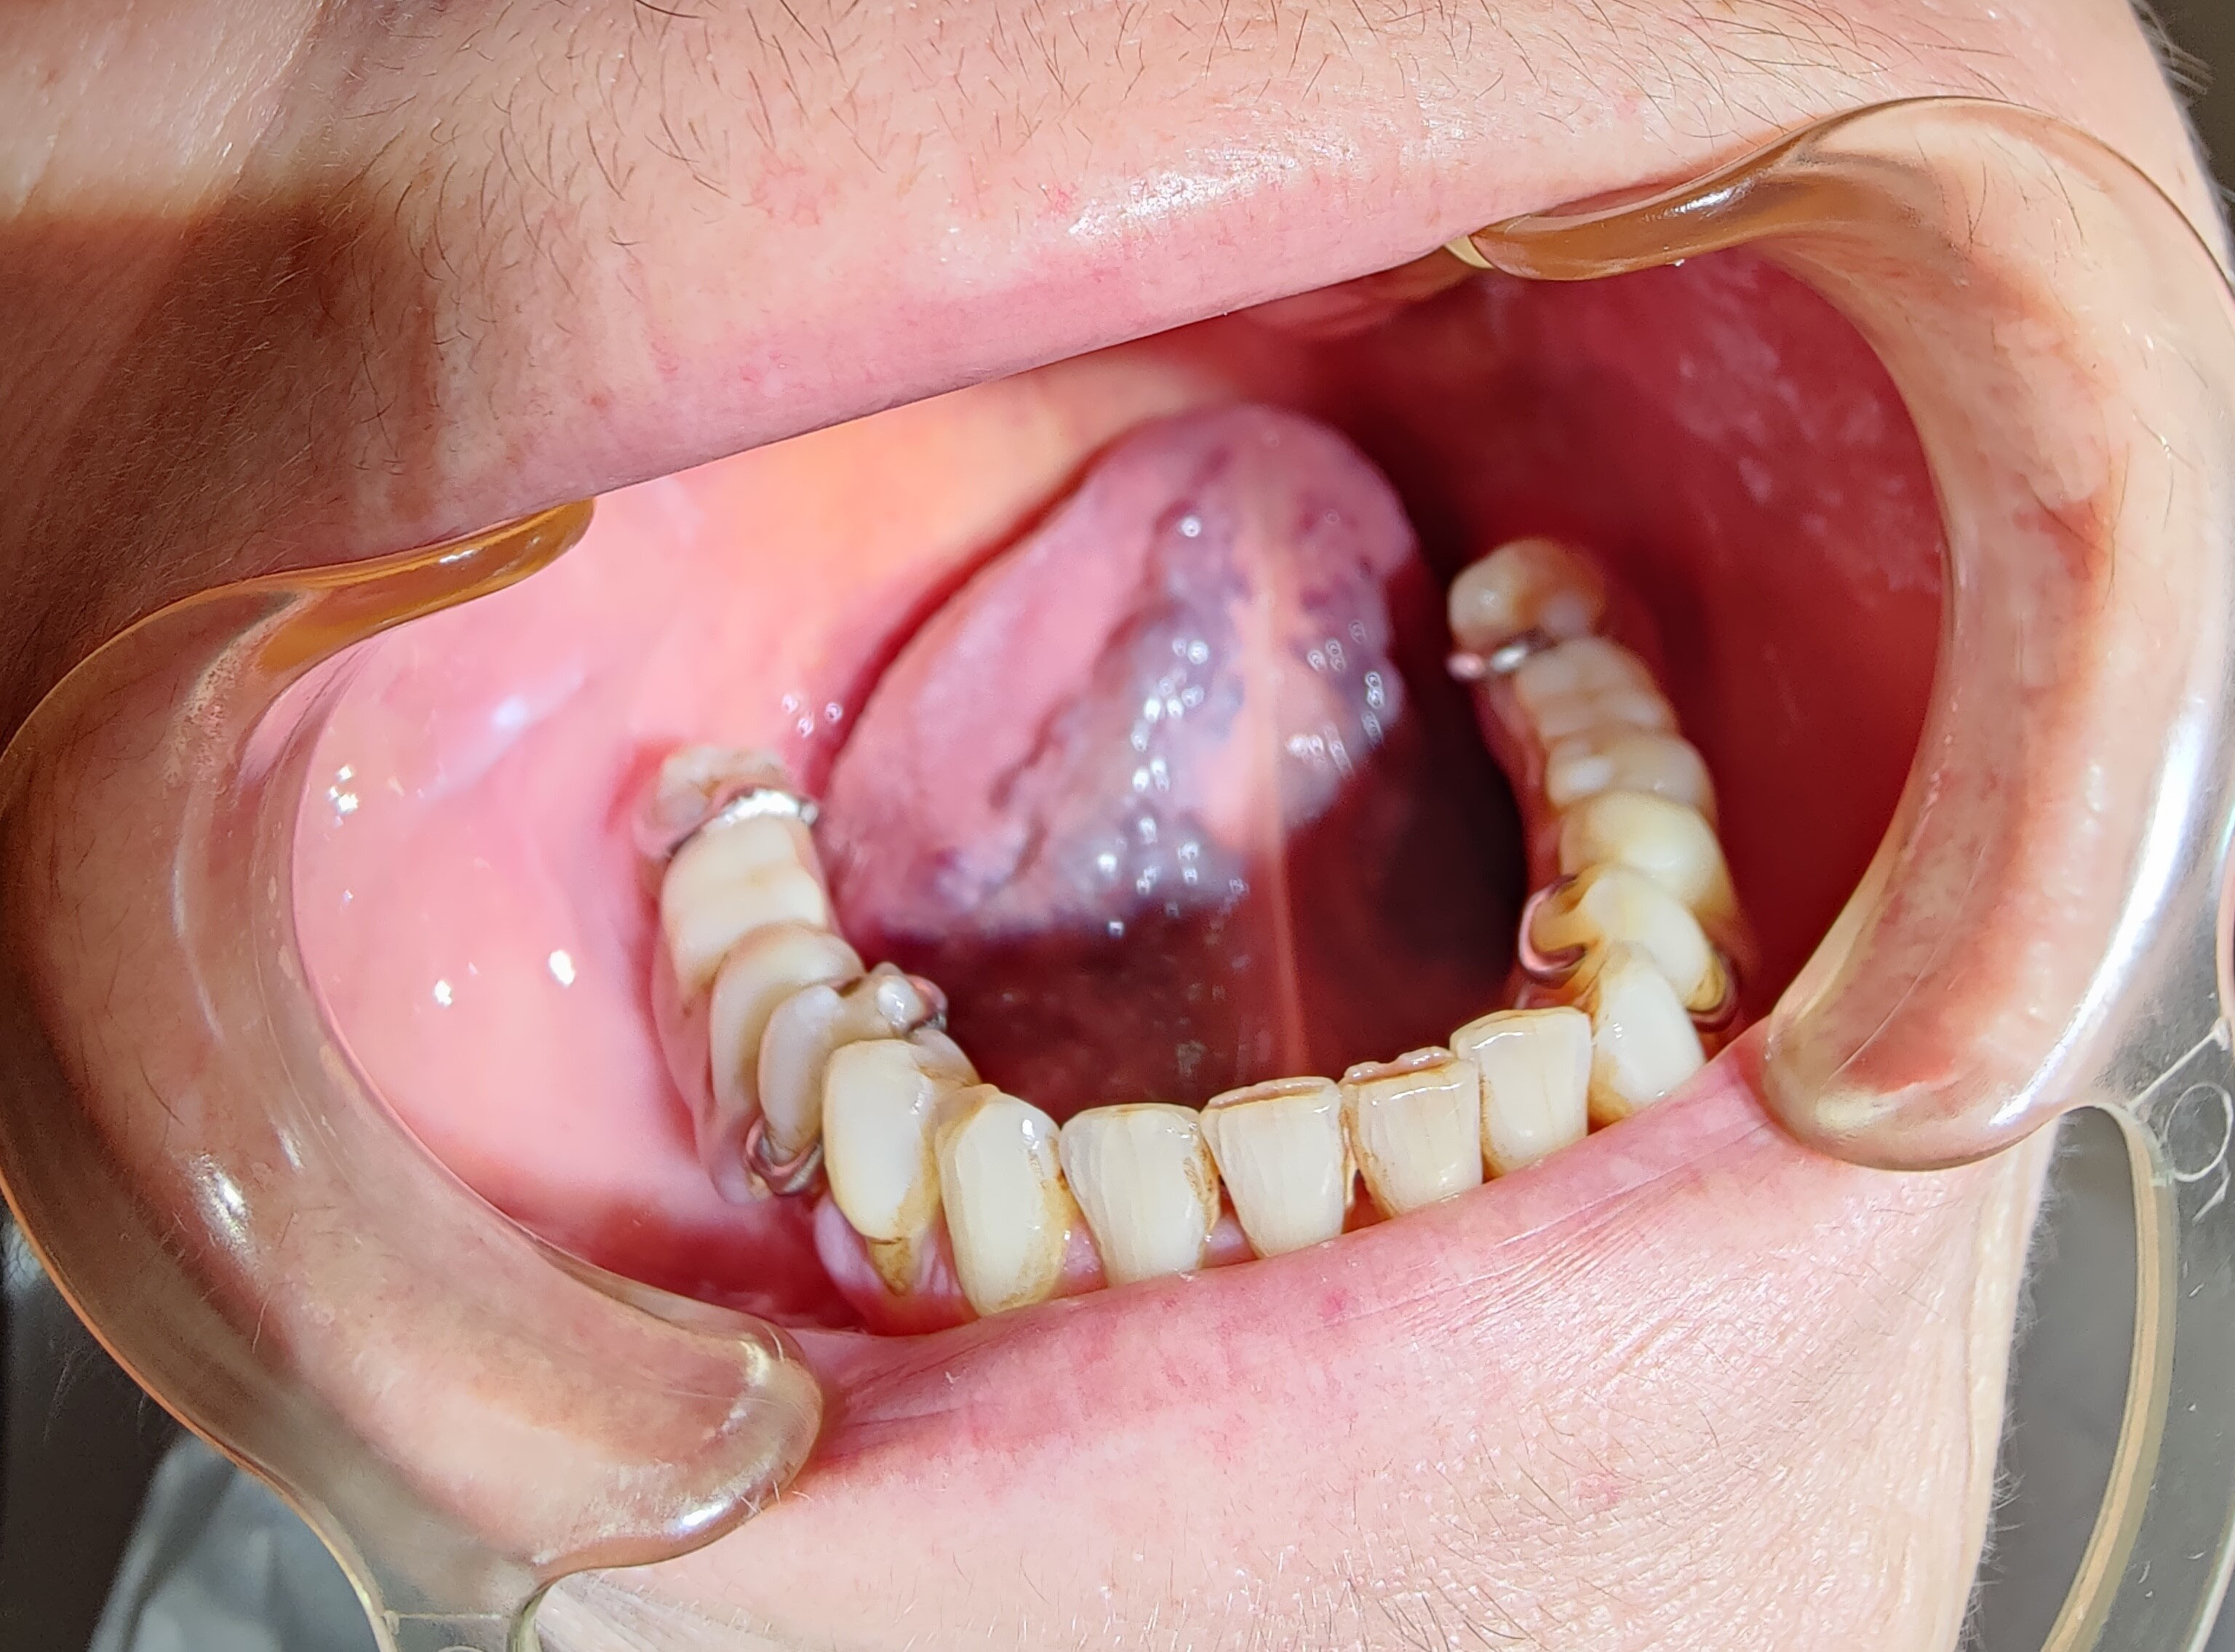

The first variants of the virus gave a characteristic picture of strawberry tongue, which occurred in 208 analyzed patients. Subsequently, depapillation (Figure 2) was identified in 86 women and 156 men. The Omicron variant caused the intensification of clinical changes on the tongue, which included geographic tongue in 65 women and 124 men with strongly marked furrows on the entire dorsal and lateral surfaces. Vascular changes on the ventral surface (Figure 3) were identified in 102 women and 46 men. Large aphthous changes were found in 106 women and 58 men, candidiasis – in 89 women and 57 men, edema – in 42 women and 52 men, herpetic lesions – in 38 women and 49 men, ulcers – in 38 women and 46 men, erosions – in 32 women and 28 men, nodular lesions (Figure 4) – in 6 women and 19 men, and necrotic changes were found in 9 women and 7 men. Enlarged fungiform papillae were reported in 189 women and 213 men.

The documentation of the group under study revealed that 94.36% of patients demonstrated enlarged fungiform papillae, 56.81% had depapillation, 48.82% had strawberry tongue, and 44.36% presented with geographic tongue.

The medical records of the patients included in the study indicated that candidiasis occurred in 29.96% of patients, herpetic lesions – in 16.19%, ulcers – in 15.96%, erosions – in 11.26%, and tongue depapillation affected 56.8% of individuals.